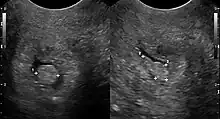

Cervical polyp on ultrasound